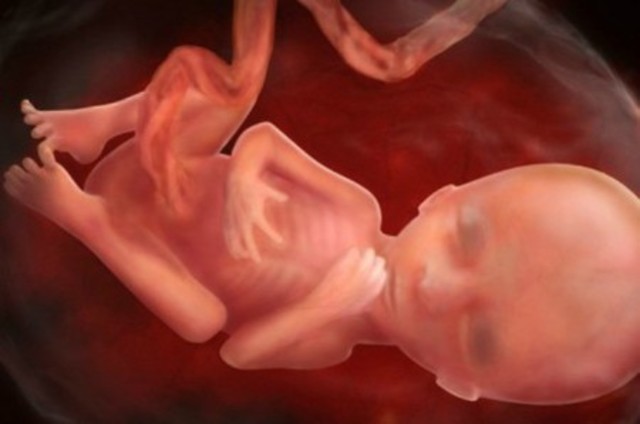

El cigoto se convierte en embrión. desarrolla el sistema circulatorio, el corazón y brotes de lo que posteriormente serán los brazos y piernas. presenta una cola que es el inicio del cordón umbilical. Se forman los dedos de las manos y pies, los labios, el hígado, orejas y ojos.

Crece un bello fino en el cuerpo y una capa de grasa que ayudará a proteger la piel del bebé cuando nazca.

Aparecen pestañas y cejas.

Inicia cambios físicos, regula actividades y momentos de sueño, los parpados se abren y se forma la retina.